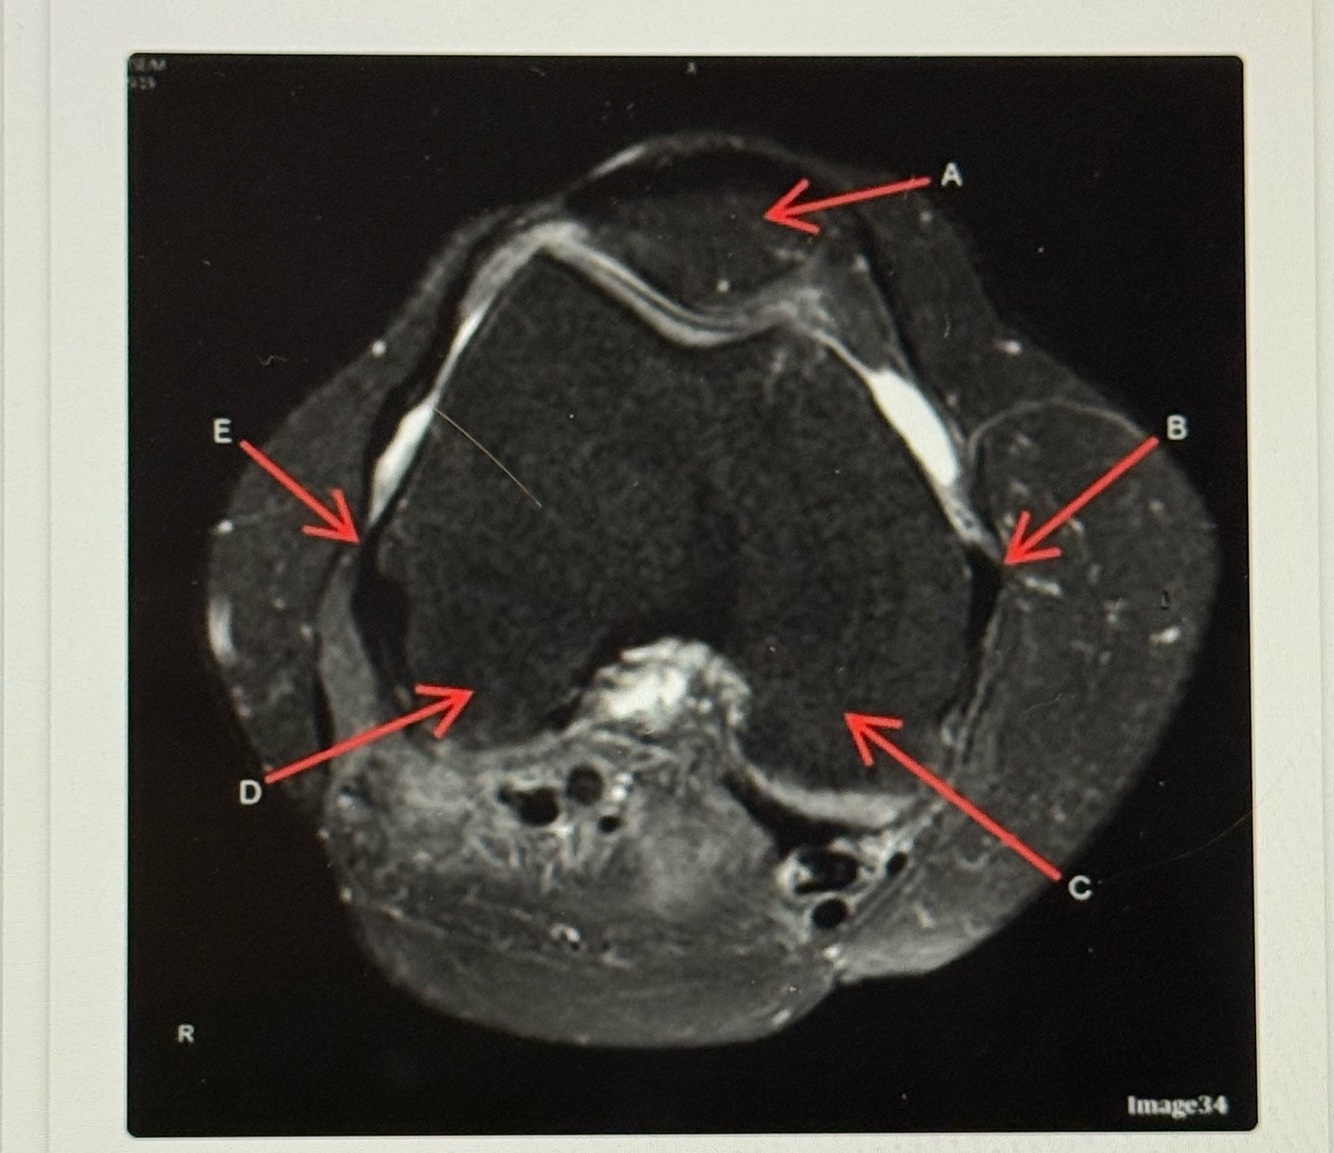

20

Q

Letter D points to the

A

Lateral femoral condyle

21

Letter C points to the

Medial femoral condyle

22

Letter B points to the

Medial

Collateral ligament (MCL)

23

Letter A points to the

Letter E points to the

Lateral collateral ligament (LCL)

25

Medial collateral ligament (MCL)

26

Letter A is pointing to the

27

Medial Meniscus

28

Tibeal plateau

29

Lateral meniscus

30

Letter F points to the